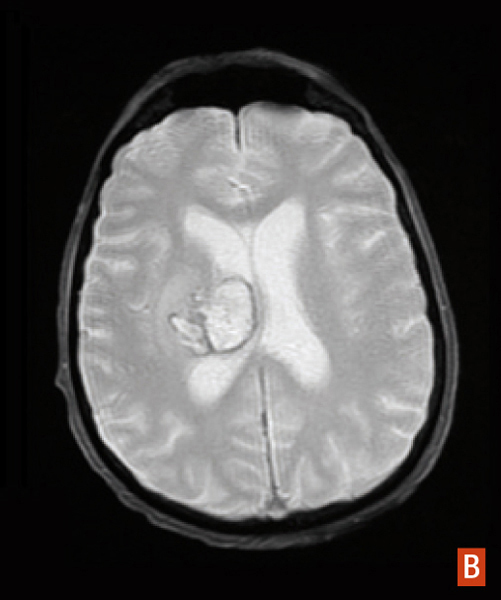

Hématome intracérébral profond

IRM cérébrale séquence T2*, hypersignal avec halo périphérique en hyposignal.